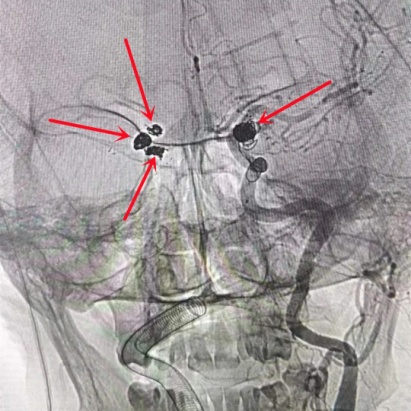

患者颅内的4个动脉瘤

刘女士颅内的4个动脉瘤处于不同位置,形状不规则,随时可能再次破裂出血的,风险极高。赵连东主任组织科内讨论,制定周密的手术方案。针对动脉瘤,通常有两种手术方式:开颅动脉瘤夹闭术和经导管颅内动脉瘤支架辅助栓塞术,因刘女士为颅内多发动脉瘤,如行夹闭术需左右两侧开颅,不仅手术创伤大,因患者身体承受能力有限,手术风险极高,而创伤小、恢复快、并发症低的介入微创治疗才是患者的最佳选择。栓塞术不需开颅,是真正的微创手术,只需要通过股动脉处做针眼大小穿刺孔便一次性处理4个动脉瘤,可谓是“一箭四雕”,但对术者的要求极高。

赵连东主任通过与患者及家属的病情沟通,并取得家属的充分信任后,决定为患者施行经导管颅内动脉瘤支架辅助栓塞术。赵连东主任经过充分的术前准备,手术立即进行,在全麻插管下为患者实施了经导管颅内动脉瘤支架辅助栓塞术,历时两个小时手术顺利完成,术后造影提示4个动脉瘤均未见血流通过,载瘤动脉通畅,4根血管上的“炸弹”被成功拆除。术后刘女士恢复良好,对赵连东主任团队赞不绝口,要知道,对于多发性动脉瘤,如果采取一次处理一个,多次手术,不仅住院时间长,花的钱多,而且在等待下次手术过程中,还有剩余动脉瘤破裂的危险。

术后影像显示患者颅内四个动脉瘤被成功栓塞